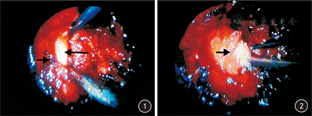

术后1年行CT扫描以评定术后硬膜外纤维化程度。纤维化程度评分方法:选取每位患者手术节段椎间盘硬膜外纤维化面积最大的CT片,并以椎管中点为中心作2条垂线,将椎管分为4个象限,每个象限内的硬膜外纤维化程度采用Ross等[5]发明的评分方法。0分:某一象限内无或仅有极少量纤维化;1分:某一象限存在纤维化组织,但面积<25%;2分:某一象限纤维化面积≥25%且<50%;3分:某一象限纤维化面积≥50%且<75%;4分:某一象限纤维化面积>75%。由1位主治医师在不知分组情况下进行评分,并由另1位副主任医师在不知分组情况下复核评分。如评分相同,则记录;如评分不同,则由第3位副主任级别进行评分,然后记录评分相同数据。见图3。

术后1年,A组硬膜外纤维化程度CT评分均数为1.80,B组为1.15。A组与B组相比,差异具有统计学意义(P<0.01),见表3及图4,图5,图6。标准化问卷统计结果:A组手术治疗满意率为75.8%(69/91),B组患者手术治疗满意率为92.2%(106/115),差异有统计学意义(χ2=10.623, P<0.01)。